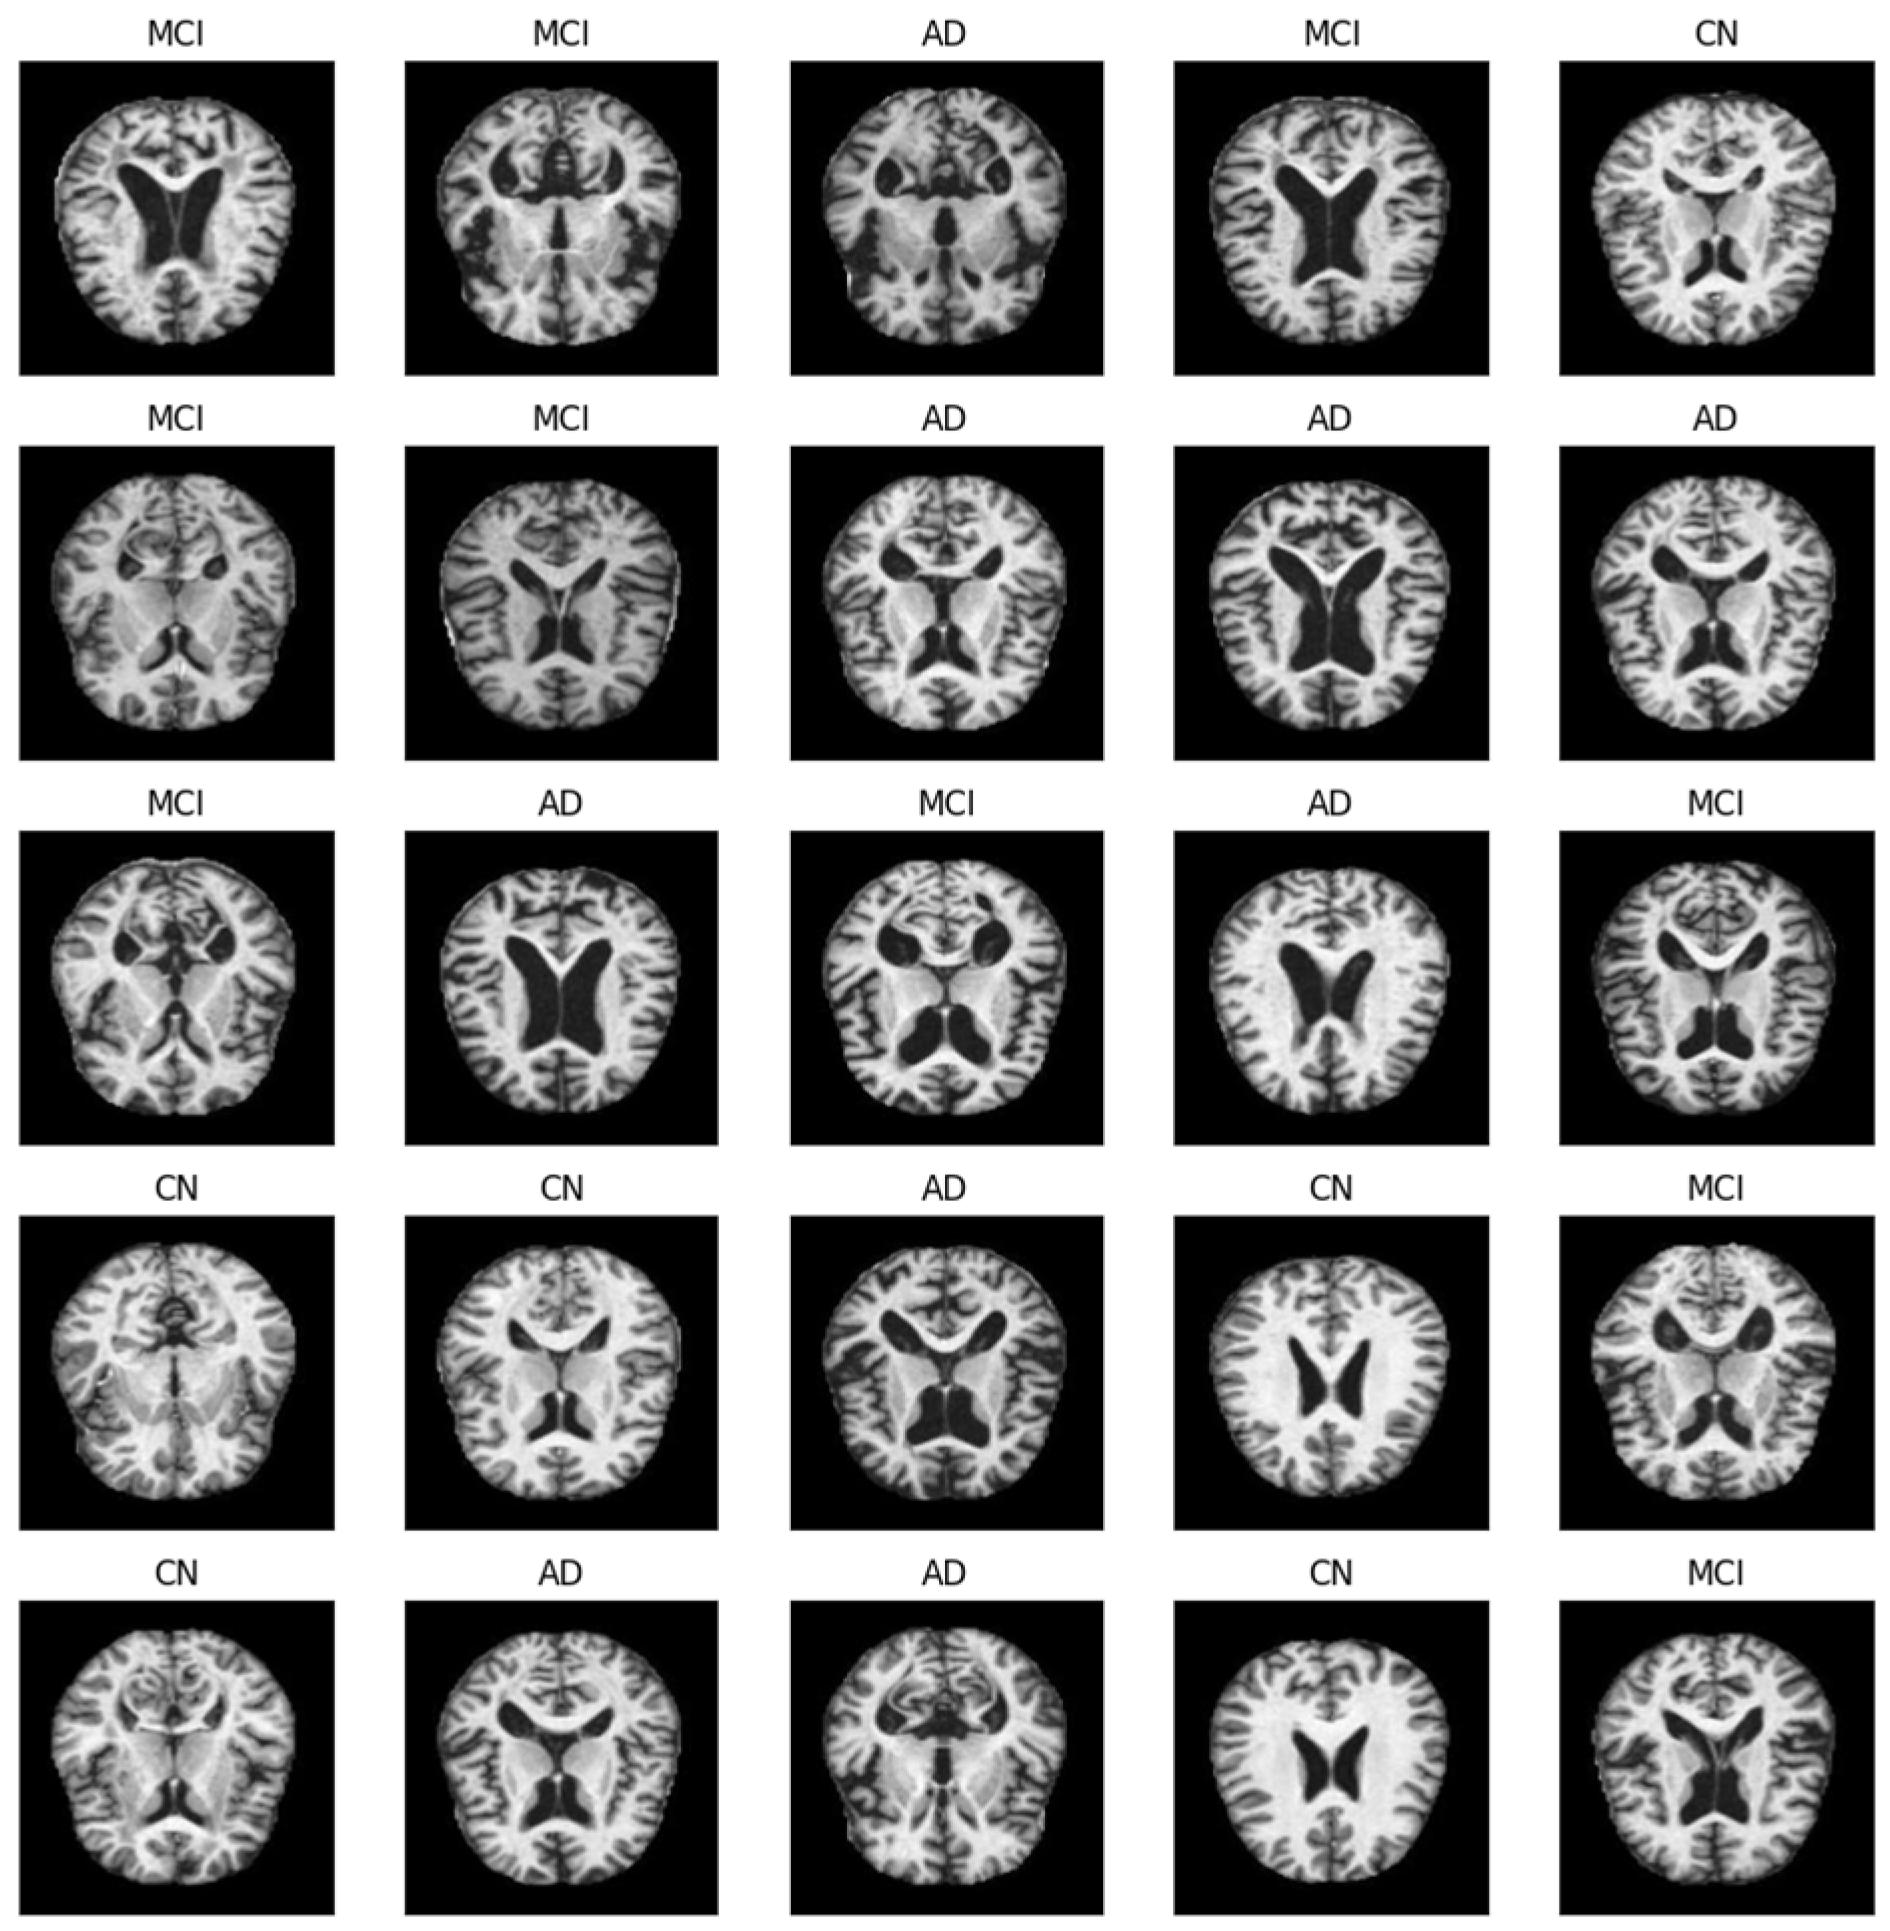

- AD—individuals diagnosed with AD and exhibiting typical signs and symptoms;

- CN—control group of CN subjects exhibiting no signs of dementia;

- MCI—individuals with subjective cognitive impairment of varying severity but without any other typical signs of dementia, whose daily activities remained mostly unaffected.

2.1.2. Data Preprocessing and Selection